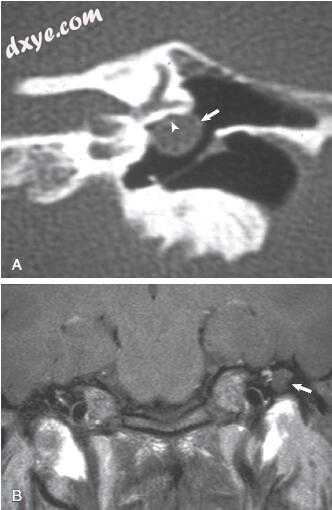

图-13. 冠状颞骨计算机断层扫描(A)和T1加权磁共振成像(B)显示胆脂瘤(箭头)侵蚀面神经管(箭头)。